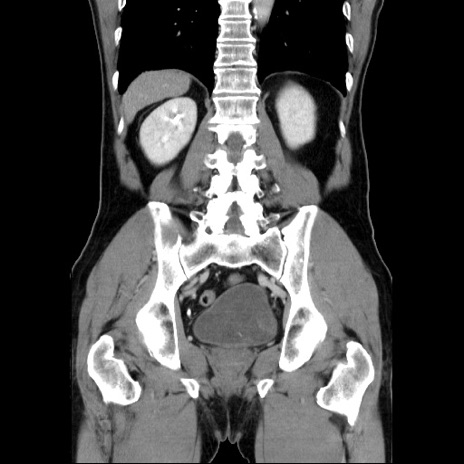

症例34(冠状断像)

【症例】60歳代 男性

【主訴】右鼠径部膨隆

【現病歴】1年程前より右鼠径部膨隆あり。自己にて還納可能だったため放置していた。3時間前より右鼠径部の脱出を認め、還納困難となり受診。

【既往歴】高血圧

【身体所見】右鼠径部に小児頭大の膨隆あり。弾性硬であり、用手還納は困難。左鼠径部にも膨隆を認める。脱出はなし。

【データ】WBC 15500、CRP 測定なし